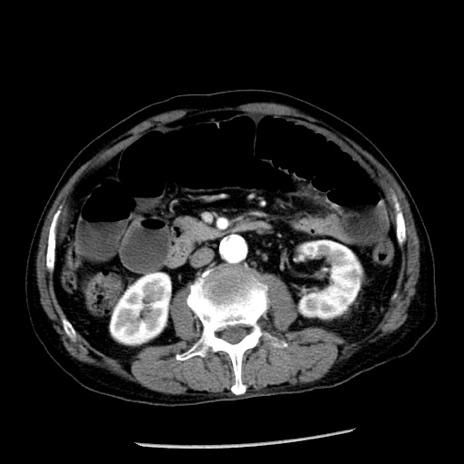

症例26(横断像)

【症例】80歳代男性

【主訴】嘔吐

【現病歴】昨晩2回嘔吐あり、今朝になっても嘔吐あり。来院。

【既往歴】胃潰瘍

【身体所見】意識清明、BT 37.6℃、BP 166/95mmHg、HR 100bpm、SpO2 97%、腹部:平坦・軟、腸蠕動音聴取良好、圧痛なし。

【データ】WBC 21900、CRP 1.46